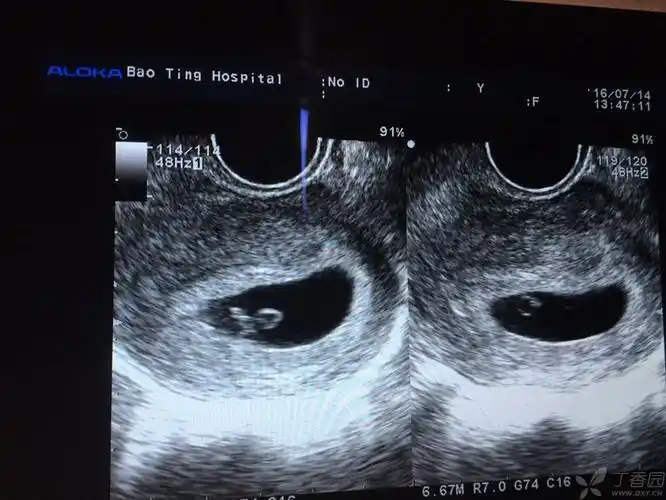

是否可以诊断早期双胎? [病例帖]

从最初b超里的一个孕囊在某一天变成了两个,哦哦,原来是双胞胎呀!

两个孕囊,两个胎盘的双胞胎

原创3张一个孕囊俩胚芽孕妈喜怀双胞胎三种双胞胎形式你了解几个